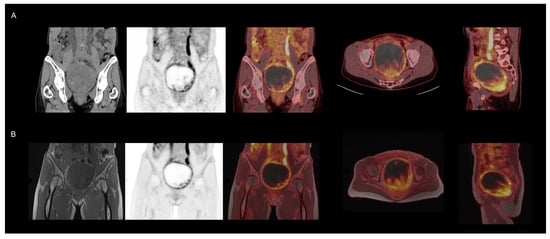

First Clinical Experiences with the Ultra-Fast Time-of-Flight BIOGRAPH One Next-Generation Hybrid PET/MRI System

by Otto M. Henriksen, Kirsten Korsholm, Annika Loft, Johanna M. Hall, Annika R. Langkilde, Vibeke A. Larsen, Thomas S. Kristensen, Caroline Ewertsen, Frederikke E. Høi-Hansen, Patrick M. Lehmann, Karen Kettless, Flemming L. Andersen, Thomas L. Andersen and Ian Law

Diagnostics 2026, 16(3), 398; https://doi.org/10.3390/diagnostics16030398 - 27 Jan 2026

Objective: We present the first clinical experience with the BIOGRAPH One next-generation PET/MRI system scanner, evaluating its performance for body and brain imaging in patients across multiple tracers. Methods: A total of 59 patients were scanned on the BIOGRAPH One PET/MRI following standard clinical PET/CT (n = 52) or first-generation PET/MRI (Biograph mMR, n = 7). Scans comprised 30 total body (TB), whole body (WB), or regional scans with [18F]FDG, and 29 brain scans with either [18F]FDG (n = 5), [18F]FE-PE2I (n = 10), [18F]FET (n = 4), or [68Ga]Ga-DOTATOC (n = 10). The PET image quality was visually assessed using a 5-point Likert scale (1 = very good to 5 = very bad) and compared with clinical scans acquired on either a current-generation digital PET/CT or a first-generation PET/MRI system, including evaluation of diagnostic concordance. PET quantification and image noise was compared in brain and WB/TB [18F]FDG PET scans. Results: PET image quality was rated as good or very good in 93% of scans with a median [inter-quartile range] score of 1.5 [1.5;2]. In 99% of cases, image quality was judged equal to or better than the clinical reference scan (median score 3 [2.5;3]). Diagnostic concordance was observed in 99% of readings. Imaging metrics revealed the anticipated regional bias in brain imaging, while no significant bias was observed in body imaging. Image noise was comparable to that observed with digital PET/CT and demonstrated superiority over first-generation PET/MRI despite potential degradation related to isotope decay in BIOGRAPH One PET/MRI acquisitions scans performed at the end of the imaging workflow. Conclusions: Within the study limitations related to sequential imaging, the BIOGRAPH One PET/MRI scanner demonstrated improved PET sensitivity and workflow potential over its first-generation predecessor, which may allow for broader clinical and research applications. Full article